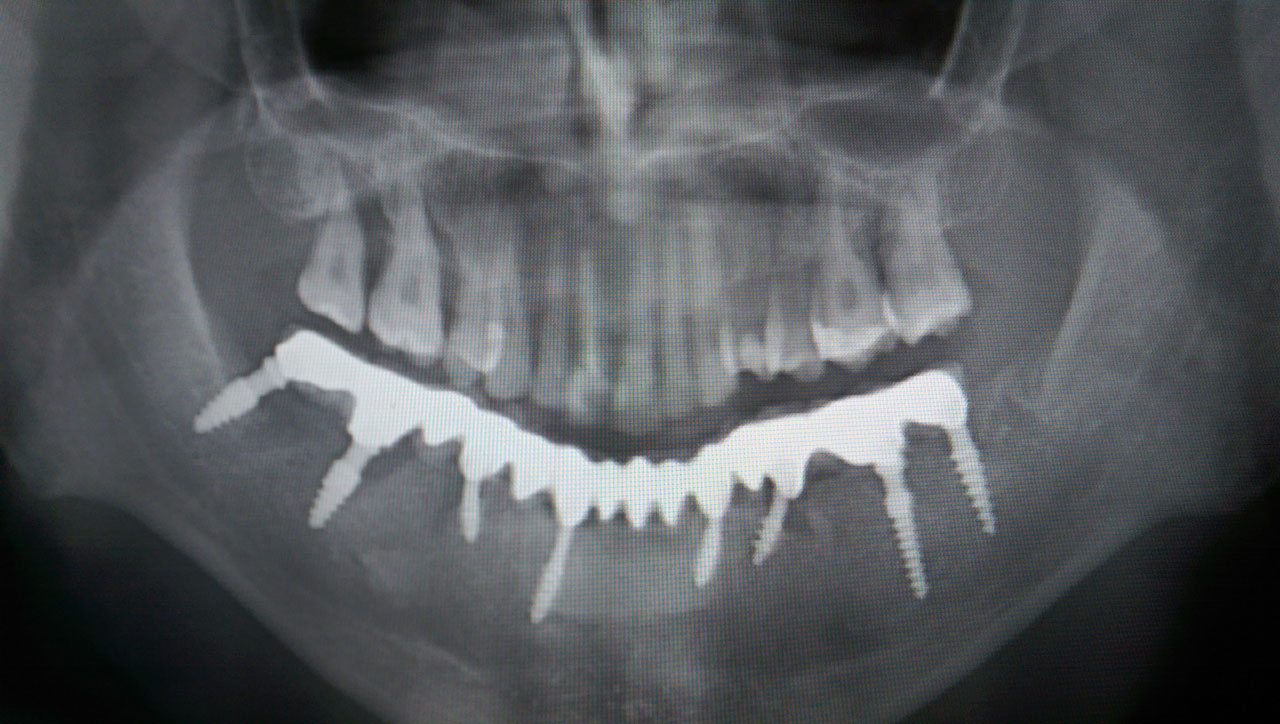

Alsó állcsont teljes rehabilitációja 72 óra alatt

Alsó állcsont teljes rehabilitációja 72 óra alatt, azonnal terhelhető implantátumokkal súlyos paradontitisben szenvedő dohányzó páciens esetében. Az alsó állcsont fogai mind mozogtak az előrehaladott fogágypusztulás miatt.

A fogakat eltávolítottuk, a gyulladt, fertőzött csontot kitakarítottuk, kifertőtlenítettük, majd azonnal implantáltunk.

Svájci, IHDE márkájú, azonnal terhelhető implantátumokat helyzetünk be, és ezekre harmadnapra rögzített, hosszútávú, fémvázas, esztétikus műanyaggal leplezett hidat ragasztottunk be.

Ezt az ideiglenes hidat a sebek gyógyulása miatt használjuk, de tartóssága miatt véglegesként is használható. A legtöbb esetben, ahogy itt is, 6 hónap múlva porcelán hídra cseréljük, a teljes gyógyulás után.